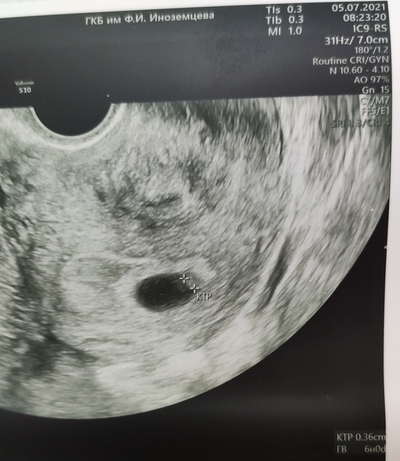

Тем не менее, работу я свою продолжаю делать, а именно - способствую появлению новой человеческой жизни в условиях лаборатории ЭКО.

Моя работа - это всегда надежды пациентов, иногда непростые истории и судьбы, это работа без права на ошибку, работа, которая всегда с тобой в голове, потому что ты всегда ждёшь - как оплодотворилось, как поделилось, как перенеслось, как прижилось или не прижилось, ну и иногда работа без выходных))

Мысли: "все ли я сделала как надо?" и "всё ли что могла?" - постоянные спутники.

Отсюда регулярное самокопание, поиски причин в случае неудач, эмоциональное выгорание. Каждый отрицательный результат - это повод для анализа проделанной работы. Особенно когда видимых причин для неудач нет.